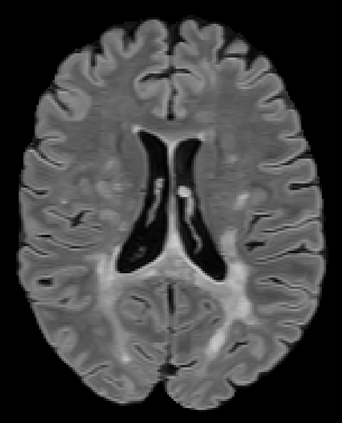

Recently, segmentation methods based on Convolutional Neural Networks (CNNs) showed promising performance in automatic Multiple Sclerosis (MS) lesions segmentation. These techniques have even outperformed human experts in controlled evaluation conditions such as Longitudinal MS Lesion Segmentation Challenge (ISBI Challenge). However state-of-the-art approaches trained to perform well on highly-controlled datasets fail to generalize on clinical data from unseen datasets. Instead of proposing another improvement of the segmentation accuracy, we propose a novel method robust to domain shift and performing well on unseen datasets, called DeepLesionBrain (DLB). This generalization property results from three main contributions. First, DLB is based on a large group of compact 3D CNNs. This spatially distributed strategy ensures a robust prediction despite the risk of generalization failure of some individual networks. Second, DLB includes a new image quality data augmentation to reduce dependency to training data specificity (e.g., acquisition protocol). Finally, to learn a more generalizable representation of MS lesions, we propose a hierarchical specialization learning (HSL). HSL is performed by pre-training a generic network over the whole brain, before using its weights as initialization to locally specialized networks. By this end, DLB learns both generic features extracted at global image level and specific features extracted at local image level. DLB generalization was validated in cross-dataset experiments on MSSEG'16, ISBI challenge, and in-house datasets. During experiments, DLB showed higher segmentation accuracy, better segmentation consistency and greater generalization performance compared to state-of-the-art methods. Therefore, DLB offers a robust framework well-suited for clinical practice.